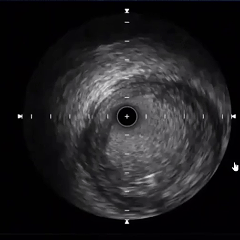

过导丝并评估血管内部情况

随后,IVUS评估显示,右冠脉管径过大,且机化血栓负荷重,如直接植入支架/放置药球可能导致支架贴壁不良/药球膨胀不全及血流恢复不佳等,决定在支架植入/药球放置前先行血栓消蚀。

4mm球囊扩张后IVUS检查

考虑到右冠状动脉内贴壁血栓负荷较重、血管直径较粗,单纯激光消蚀范围有限,常规手动血栓抽吸亦难以完全清除附壁血栓,术者团队决定送入机械血栓抽吸导管反复抽吸血栓。术后IVUS复查,血管主腔形成,但局部仍存在双腔/多腔通道结构,主腔在所有通道中直径最大。

血栓抽吸后IVUS复查

充分血栓抽吸后复查IVUS,提示第二转折处狭窄部位的低密度血栓已显著减少,局部血管直径为5.5 mm。考虑到该位置植入支架存在技术局限及潜在疗效不佳风险,经综合评估后决定采用药物球囊治疗。